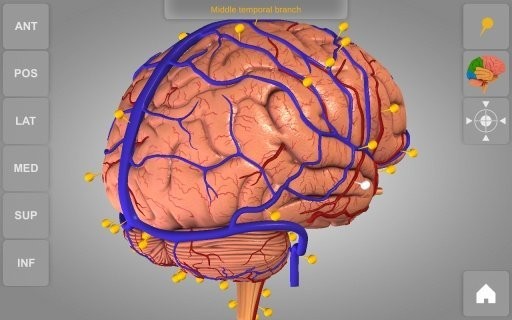

您还可以将实体模型转动到随意视角并扩大和变小

检索解剖结构名字并表明三维部位

开启/关掉不一样的解剖系统软件

1、详尽的3D身体解剖实体模型

2、高像素画面质量,更强的视觉盛宴

3、解剖结构附带对应的文字描述